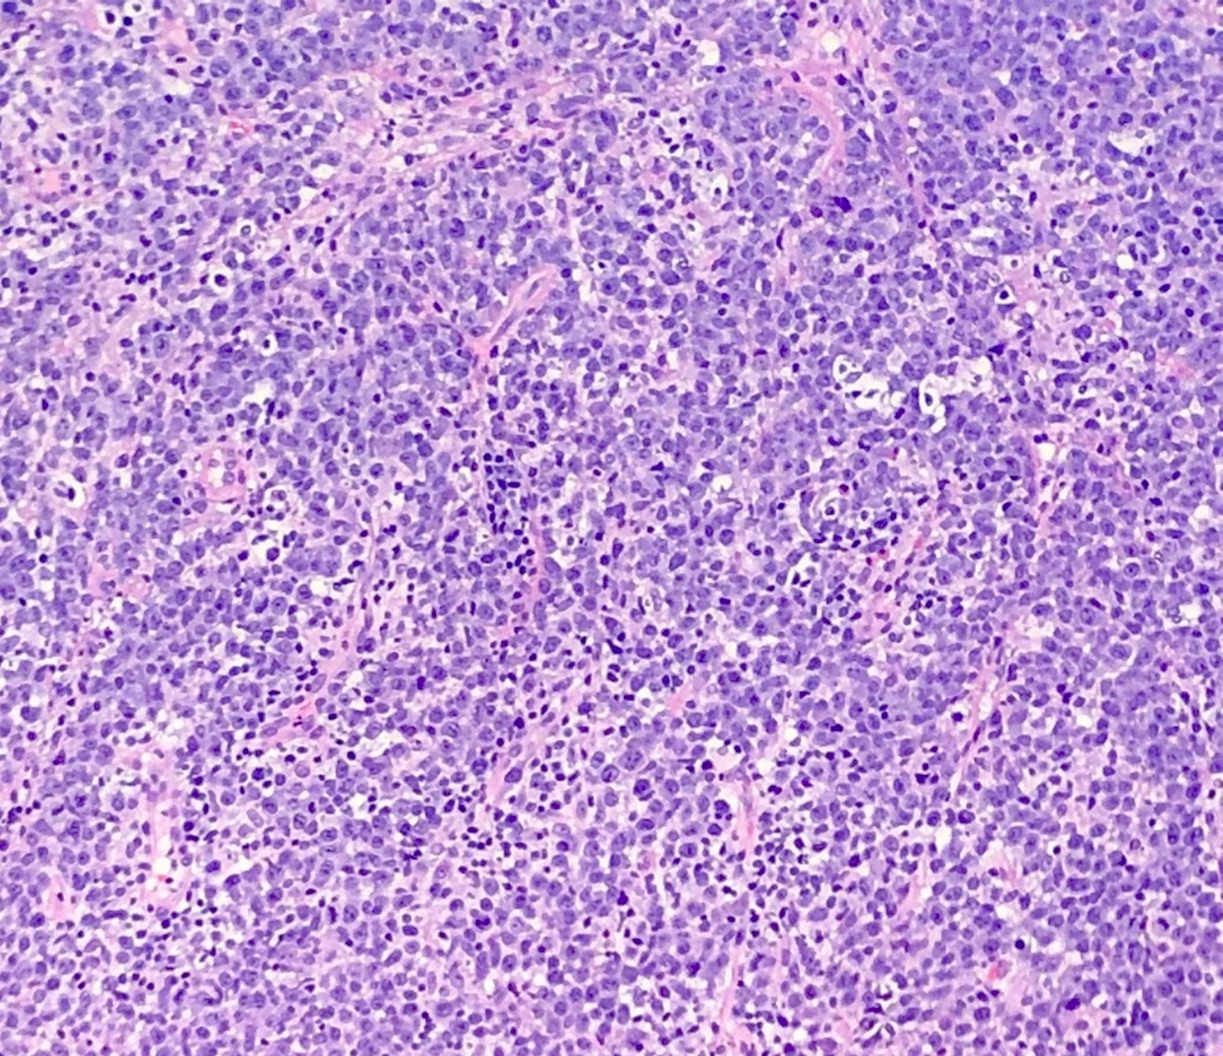

Microscopic (histologic) description

- Partial or complete effacement of normal tissue architecture by a diffuse infiltrate of large (or occasionally medium size) atypical B lymphoid cells with vesicular chromatin and prominent nucleoli

- Large is defined as nucleus size ≥ histiocyte nucleus or > 2 lymphocyte nuclei

- Morphologic variants:

- Immunoblastic variant: single central nucleolus

- Centroblastic variant: 2 - 4 nucleoli

- Anaplastic variant: anaplastic nuclei, can mimic anaplastic large cell lymphoma or Reed-Sternberg cells

Microscopic (histologic) images